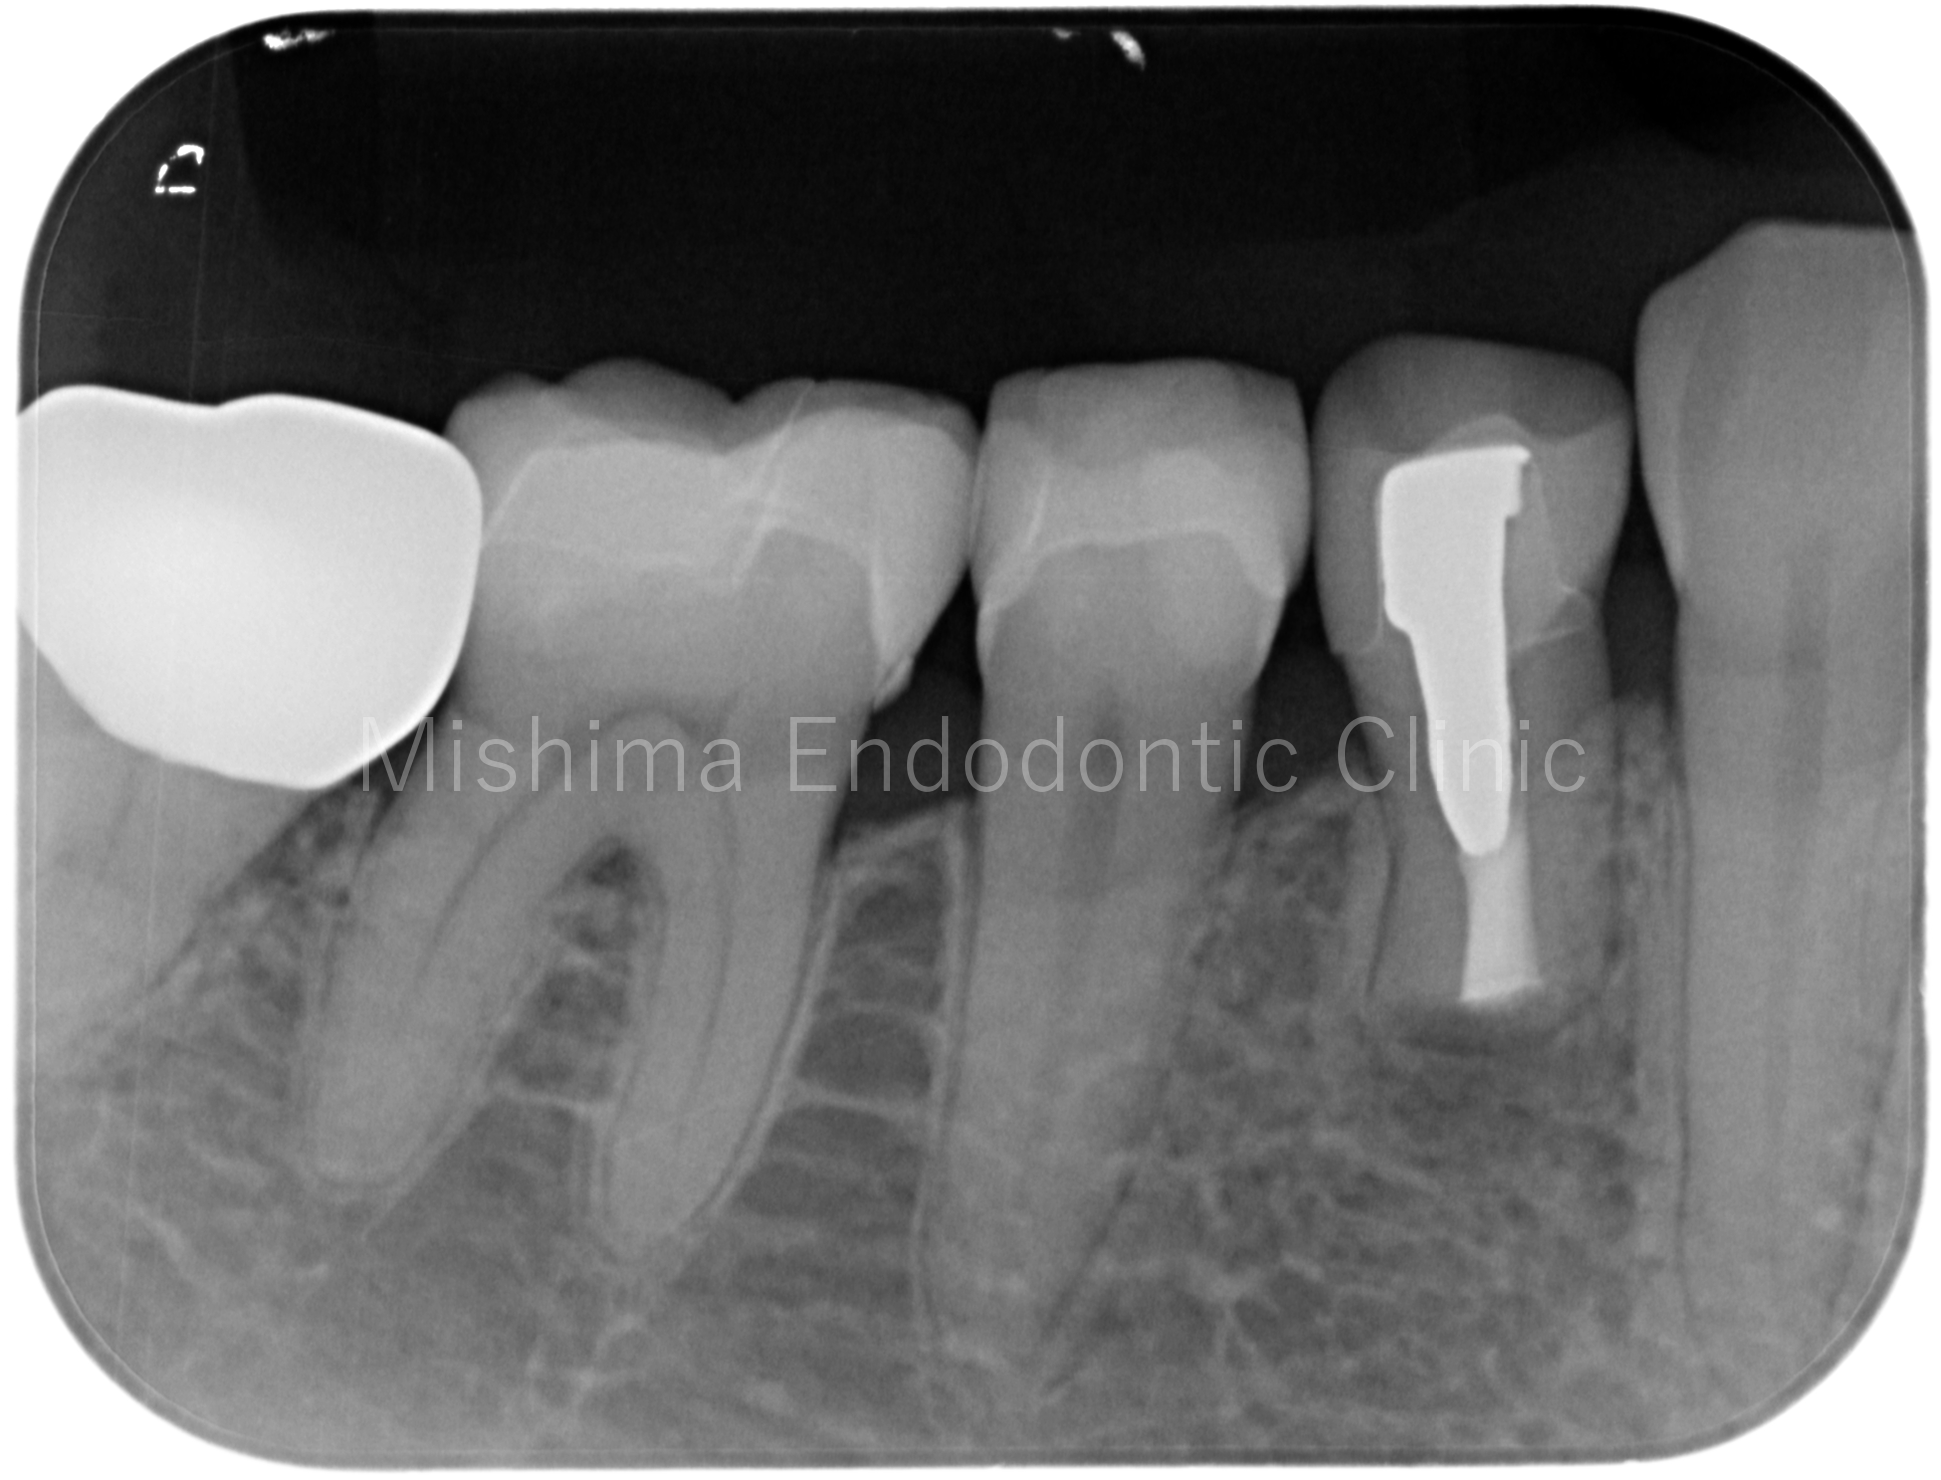

Before

| 主訴 | 他院にて歯根端切除術を受けたが、腫れて痛くなってきた |

| 治療内容 | 他院にて右上1、2、左上2の3本が歯根端切除術の既往あり。再歯根端切除術にて対応。 |